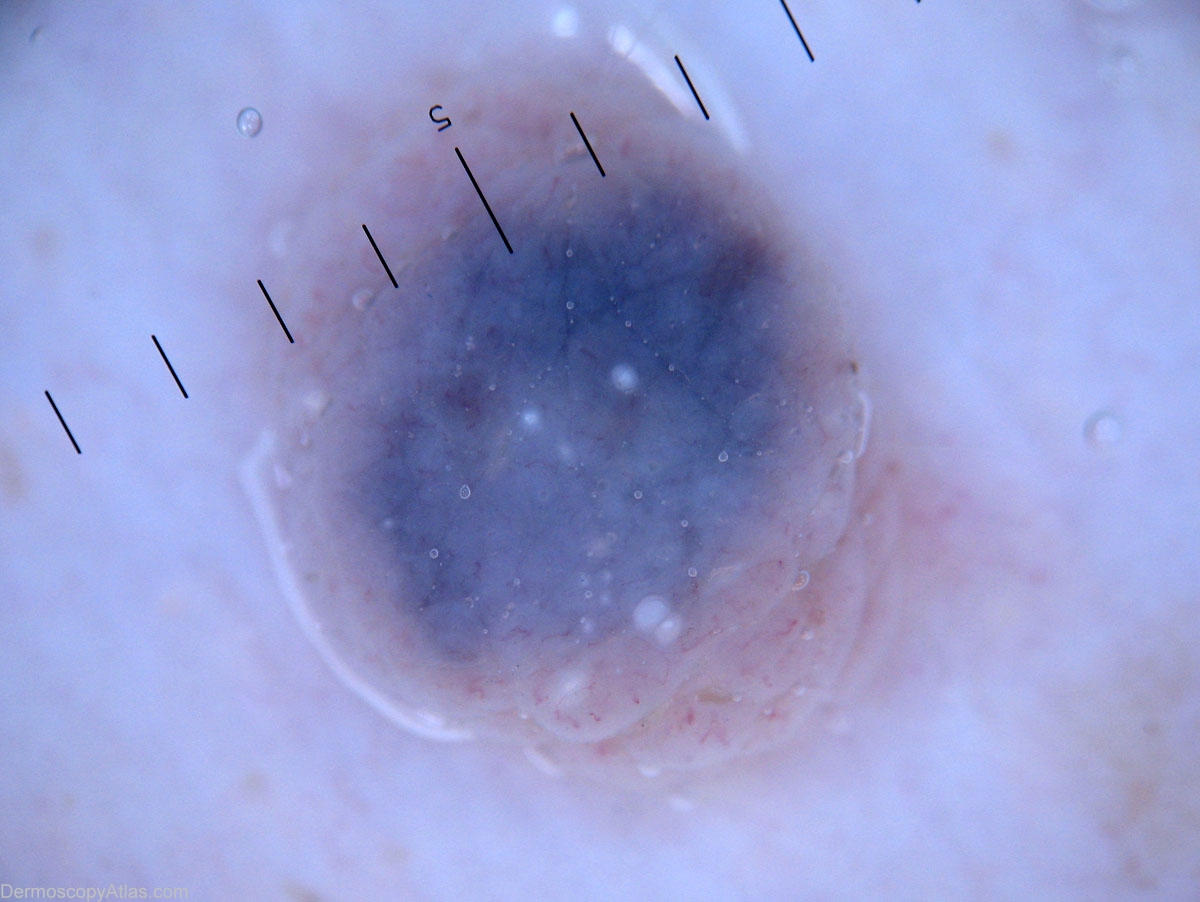

Diagnosis - Nevus dermal

Diagnosis: Nevus dermal